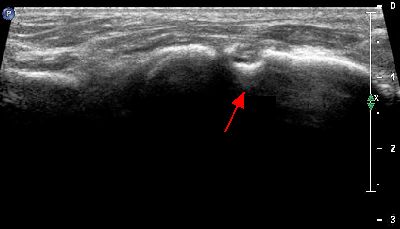

Becco osteofitico della 1a articolazione metatarso-falangea becco osteofitico prima metatarso-falangea